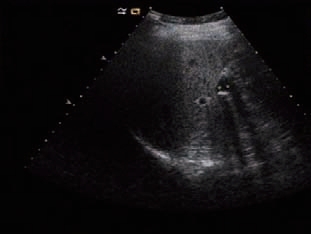

1)胆囊腔内高/强回声团。胆囊结石与周围液性胆汁声阻抗差较大,使得胆囊结石的边界可清楚显现。由于结石本身的形状、结构和成分不同,其回声形态可有较大差别。结构较致密且表面较光滑的结石,表现为新月形强回声(图5-6);结构较松散的结石,由于透声性好,结石的全貌均可被显示,呈满月形强回声(图5-7);数个堆积在一起的小结石可产生堆积状、沙堆状强回声(图5-8)。

图5-6 胆囊致密结石(新月形)及声影